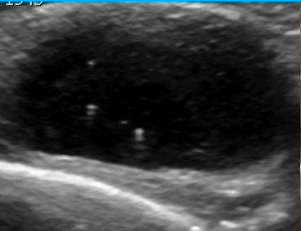

<p>Artefacto más evidente en este quiste</p>

Artefacto más evidente en este quiste

Refuerzo acústico posterior